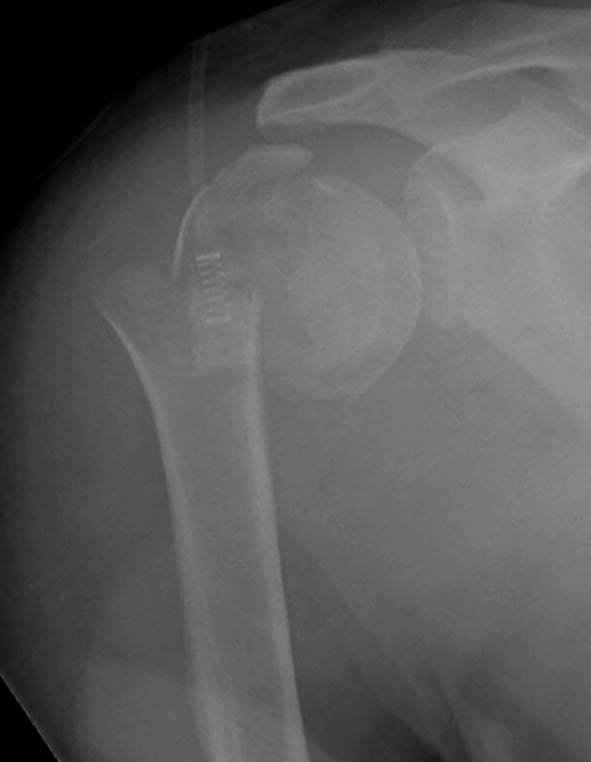

Re: Оскольчатый перелом шейки, головки плечевой ко

Второй случай, для лечения перелома проксимального

плеча применили пластину "Hand Innovation"

Пластина имеет преимущества перед другими "Locking

Implants", потому что пластину можно уложить намного ниже чем другие пластины и имеется возможности проведения шурупов под 130 градусным углом, таким образом можно уменьшить операционный разрез в проксимальной части.

Прооперирован вчера на 13 день после поступления.

Больному 41 и из-за гемодинамической нестабильности в течение первых 7 дней был в реанимации под интубационной седацией.

Извиняюсь за качества снимков, обычный больной в 300 фунтов, портативным ренген аппаратом не пробить.